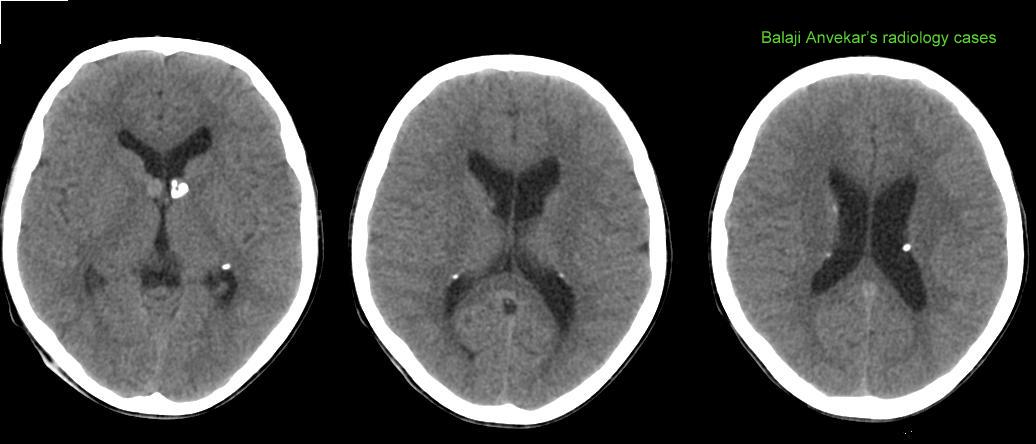

Tuberous Sclerosis Ct

Tuberous sclerosis ct. Tuberous sclerosis is a rare genetic disorder that causes noncancerous benign tumors unexpected overgrowths of normal tissue in parts of the body. Tuberous sclerosis is a rare genetic condition that causes noncancerous tumors in your brain other organs and skin. Learn how its treated. Information for parents on tuberous sclerosis.